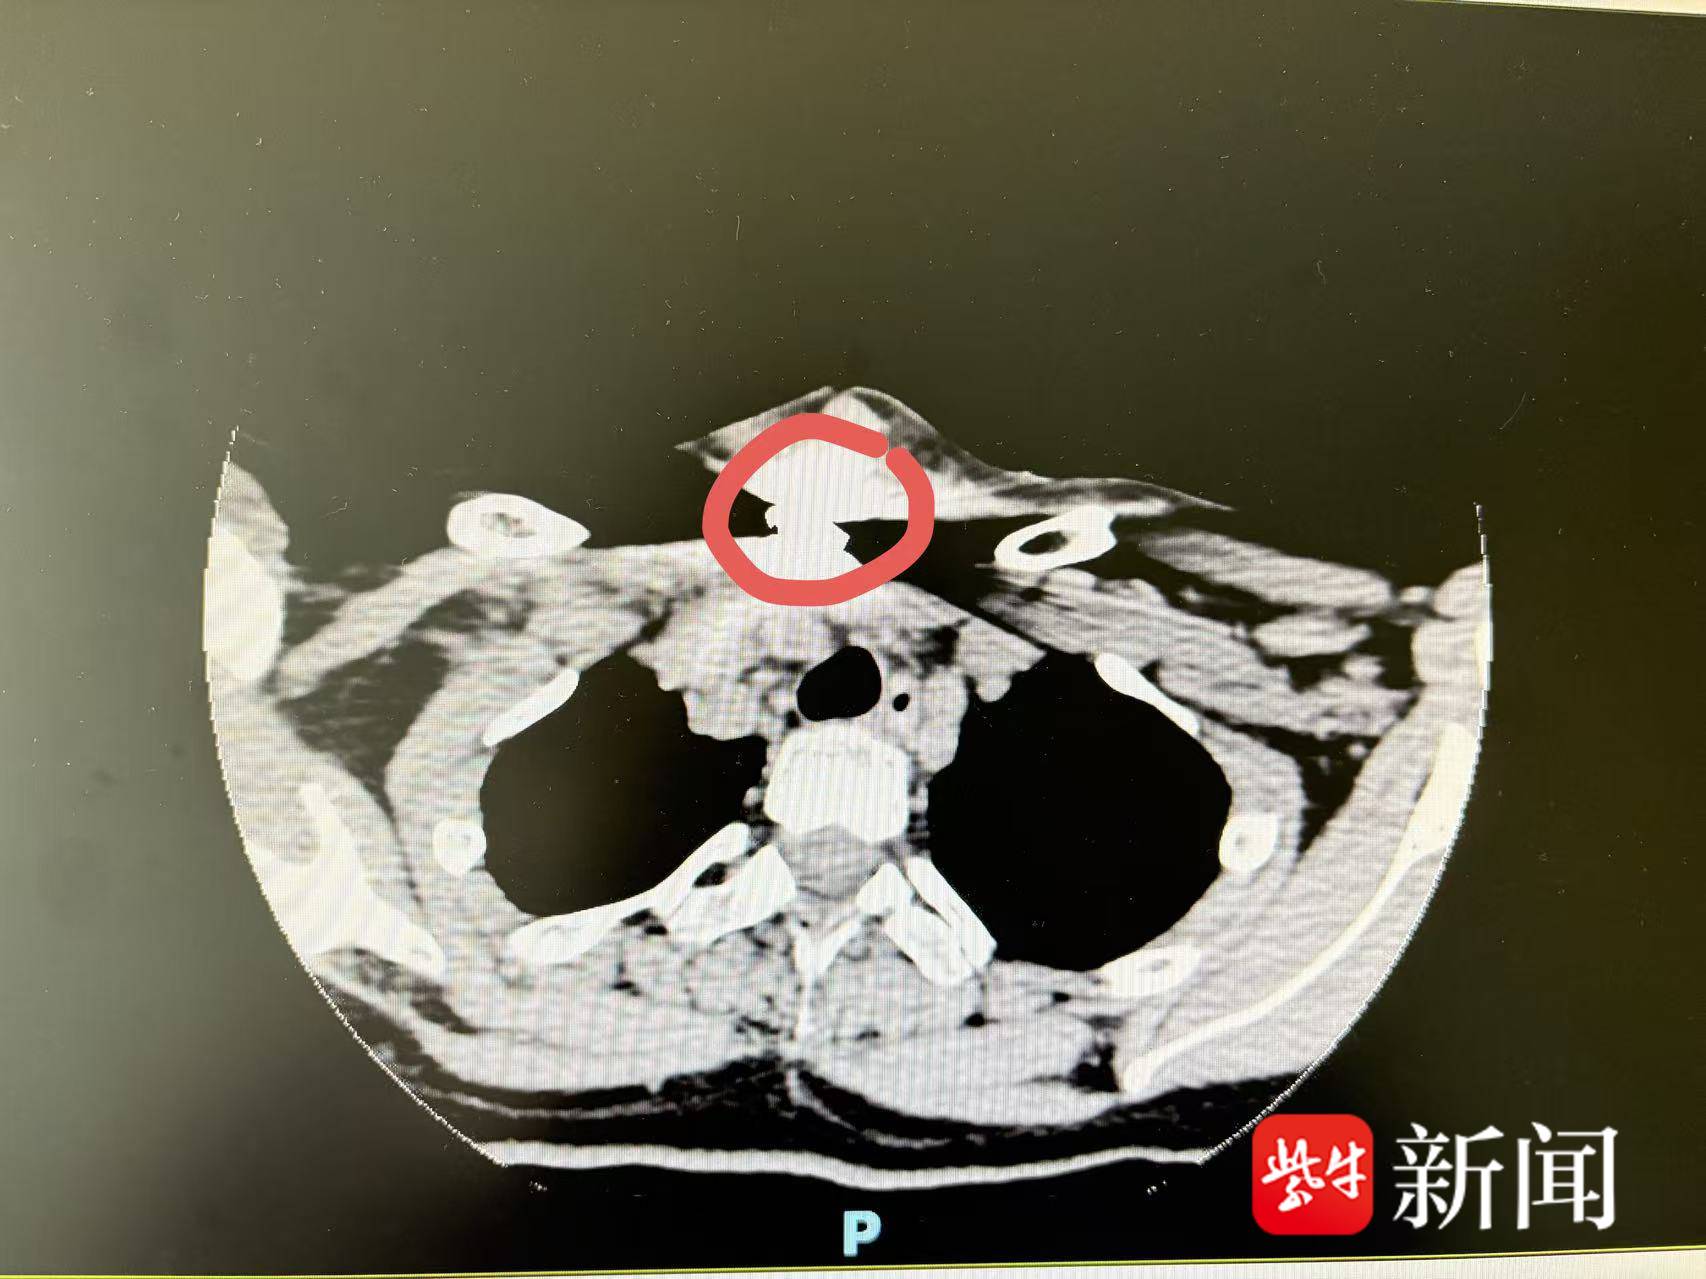

原来,颈部CT显示这枚大小约1×2cm的零件出现在T2-3水平颈根部,周围组织的肿胀和积气,最致命的是它深深嵌入了颈部的“生命禁区”,紧邻大血管、神经和气管,非常危险。